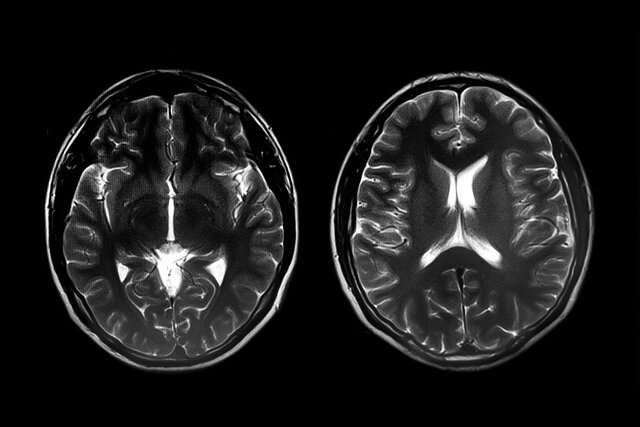

طی این مطالعه محققان ۳۸۴ خواهر و برادر را مورد بررسی قرار دادند که یکی از آنها که بزرگتر بود مبتلا به اختلال طیف اوتیسم تشخیص داده شده بود. تحقیقات قبلی این محققان نشان داده بود که اگر خواهر و برادر بزرگتر یک فرد سطوح بالاتری از ویژگیهای اختلال طیف اوتیسم داشته باشند، احتمال ابتلای خواهر و برادرهای کوچکتر به اختلال طیف اوتیسم بیشتر است. طی این مطالعه محققان تصویرسازی تشدید مغناطیسی (MRI) را روی مغز خواهر و برادر کوچکتر در سنین ۶، ۱۲ و ۲۴ ماهگی انجام دادند.

در میان ۸۹ خواهر و برادر کوچکتر مبتلا به اختلال طیف اوتیسم، آنهایی که خواهر و برادرهای بزرگترشان دارای ویژگیهای شدید اختلال طیف اوتیسم بودند، حجم و سطح مخ بیشتری داشتند که این قسمت نیز گفتار، فکر، احساسات، خواندن، نوشتن و یادگیری را کنترل میکند. از طرفی سطح بزرگتر در قسمتی از قشر بینایی برای تشخیص اشیا مهم است و اتصالات کمتر بالغ در بخش پشتی جسم پینهای که قشر بینایی چپ و راست مغز را به هم متصل میکند، در توجه بصری نقش دارد.